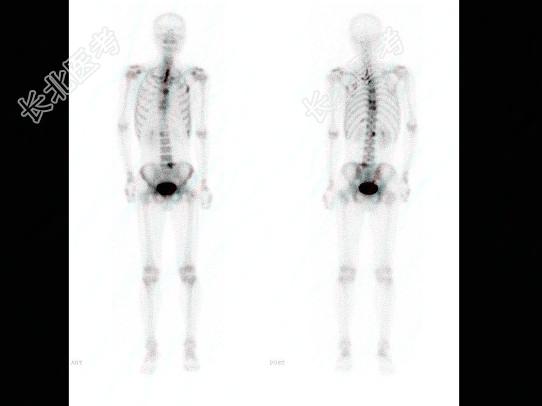

多项选择题男,42岁, 胆囊癌术后1年,无明显不适, 行全身骨显像如图,可能的诊断是 ( )

A、无明显“冷区”改变

B、有“领带征”

C、有“甜面圈”征象

D、多发骨转移改变征象

E、大致正常的影像